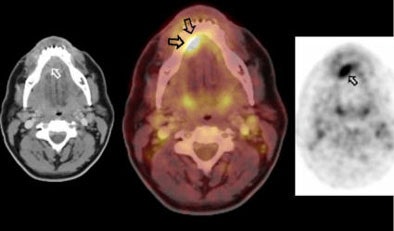

![]() |

| A 48-year-old male with carcinoma at the base of the tongue. CT and PET images (left and right, respectively) show the pathology. However, the fused PET/CT image indicates osseous infiltration, which was later confirmed by histological pathology. Images courtesy of Dr. Patrick Veit, the University Hospital of Essen, and the ECR. |